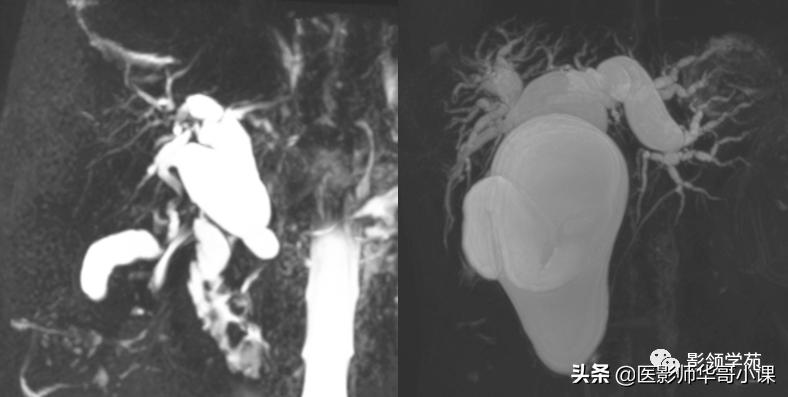

2、“中心点征”是又一重要的征象,是指囊肿阴影内的小点状软组织影像,平扫密度等于或高肝实质,在T2WI序列上呈环状低黑信号,中央区呈圆柱稍高信号,其病理基础是门静脉分支被胆管扩张的囊壁包绕,并在切面上呈轴位投影。Seth等认为“中心点”征象的出现足准确的诊断本病。

磁共振胰胆管造影(MRCP)

- MRCP是一种有效的检查方法,可清楚地了解肝外及肝内胆管的形态。根据重T2 权重序列的静态水(包括胆管和胰管内分泌物)表现为高信号,而实质性器官为低信号,流动的血液因为流空效应而无信号,因而MRCP不需要造影剂就可以获得良好的对比。可显示肝内胆管扩张的部位、大小以及有无结石存在,且有三维结构形态。并可发现本症并不合并胰胆管合流异常,此为与先天性胆管扩张症区别之一。后者可合并肝内胆管的扩张,且几乎均存在胰胆合流异常,而先天性肝内胆管扩张症则不合并胰胆合流异常。Caroli病多无明显的肝外胆管的狭窄和梗阻征象。许多学者认为本法可以作为Carolis病的首选方法。